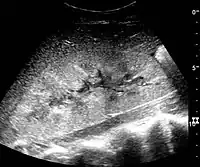

In medical imaging, the acute changes in the kidney are often examined with renal ultrasonography as the first-line modality, where CT scan and magnetic resonance imaging (MRI) are used for the follow-up examinations and when US fails to demonstrate abnormalities. In evaluation of the acute changes in the kidney, the echogenicity of the renal structures, the delineation of the kidney, the renal vascularity, kidney size and focal abnormalities are observed.[16] CT is preferred in renal traumas, but US is used for follow-up, especially in the patients suspected for the formation of urinomas. A CT scan of the abdomen will also demonstrate bladder distension or hydronephrosis.

Renal ultrasonograph of acute pyelonephritis with increased cortical echogenicity and blurred delineation of the upper pole.[16]